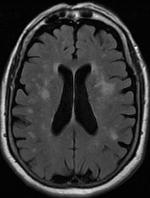

Axial T2 FLAIR sequence MR image of a middle-aged man with leukoaraiosis.

Leukoaraiosis is a particular abnormal change in appearance of white matter near the lateral ventricles. It is often seen in aged individuals, but sometimes in young adults.[1][2] On MRI, leukoaraiosis changes appear as white matter hyperintensities (WMHs).[3][4] On CT scans, leukoaraiosis appears as hypodense periventricular white-matter lesions.[5]

These white matter changes are also commonly referred to as periventricular white matter disease, or white matter hyperintensities (WMH), due to their bright white appearance on T2 MRI scans. Many patients can have leukoaraiosis without any associated clinical abnormality. However, underlying vascular mechanisms are suspected to be the cause of the imaging findings. Hypertension, smoking, diabetes,[3] hyperhomocysteinemia, and heart disease are all risk factors for leukoaraiosis.